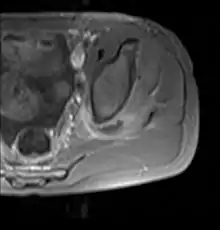

يعتمد تشخيص التهاب العضلات التقيحي على الفحص الاكلينيكي والتاريخ المرضي للمريض. ويظل التصوير بالرنين المغناطسي هو الفحص الأكثر دقةَ لتحديد الإصابة بهذا المرض.[3]

غالبًا ما تتسبب البكتيريا المكورة العنقودية الذهبية في التهاب العضلات التقيُّحي.[5] يمكن أن تؤثر العدوى على أي عضلة هيكلية، ولكنها غالبًا ما تصيب مجموعات العضلات الكبيرة مثل عضلات الفخذ أو العضلات الألوية.[4][6][7]